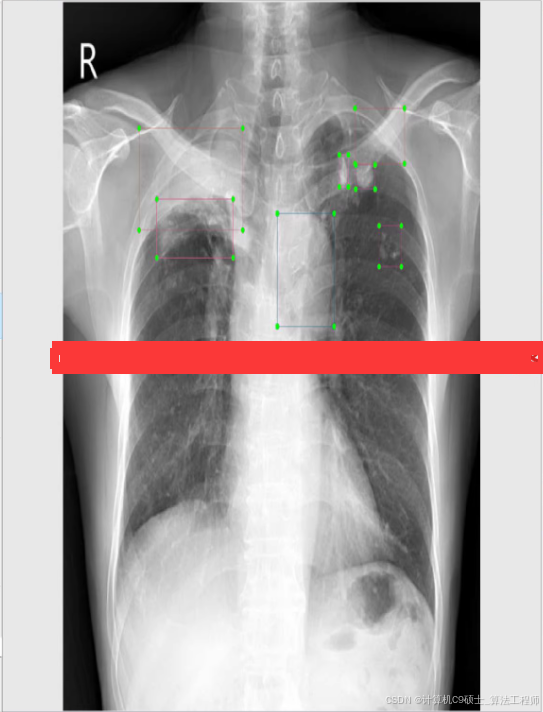

使用YOLOv8来训练——心胸肺CT检测数据集,并使用训练好的模型进行预测。

具体说明如何利用YOLOv8这一工具对包含约4100张心脏与胸部影像的心脏及胸部相关CT检测数据集进行系统性训练,并完整提供相应的训练代码及操作指南。

数据集描述

该数据集包含以下信息:

- 样本规模:4100幅图像

- 分类:12类